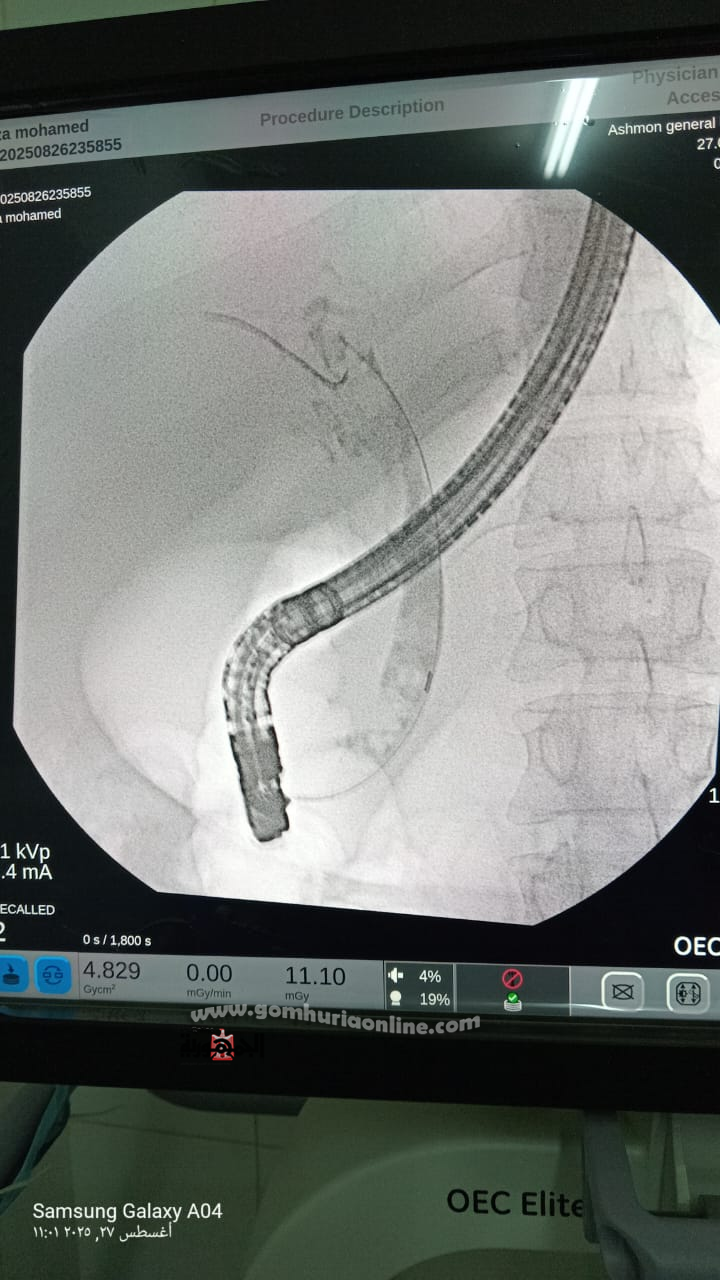

"نجاح أول حالة منظار ERCP بالقناة المرارية في مستشفى أشمون العام"

حققت مديرية الشئون الصحية بالمنوفية إنجازًا طبيًا غير مسبوق، حيث نجح الفريق الطبي بمستشفى أشمون العام بقيادة الدكتور إبراهيم ناصر مدير المستشفى، في إجراء أول حالة منظار للقناة المرارية (ERCP) داخل مستشفيات المحافظة، بعد أن كان هذا النوع من التدخلات يجرى فقط في معهد الكبد.

العملية تمت على يد فريق طبي متميز ضم كلا من الدكتور عبدالعليم هلال ، الدكتور أحمد هلال ، الدكتور محمد ممدوح ، الدكتور علاء عبد ربه ، والدكتور أحمد تعيلب وبمشاركة فريق تمريض العمليات وقسم الجراحة المتميز، حيث نجح الفريق في إزالة الدعامة القديمة، استخراج الحصوات من القناة المرارية، وتركيب دعامة جديدة بنجاح.

كما ساهم وصول جهاز المنظار الجديد المتبرع به يوم الاثنين الماضي في إتاحة الفرصة للمستشفى لإجراء العملية بدقة عالية داخل المحافظة دون الحاجة لتحويل الحالات لمراكز خارجية.